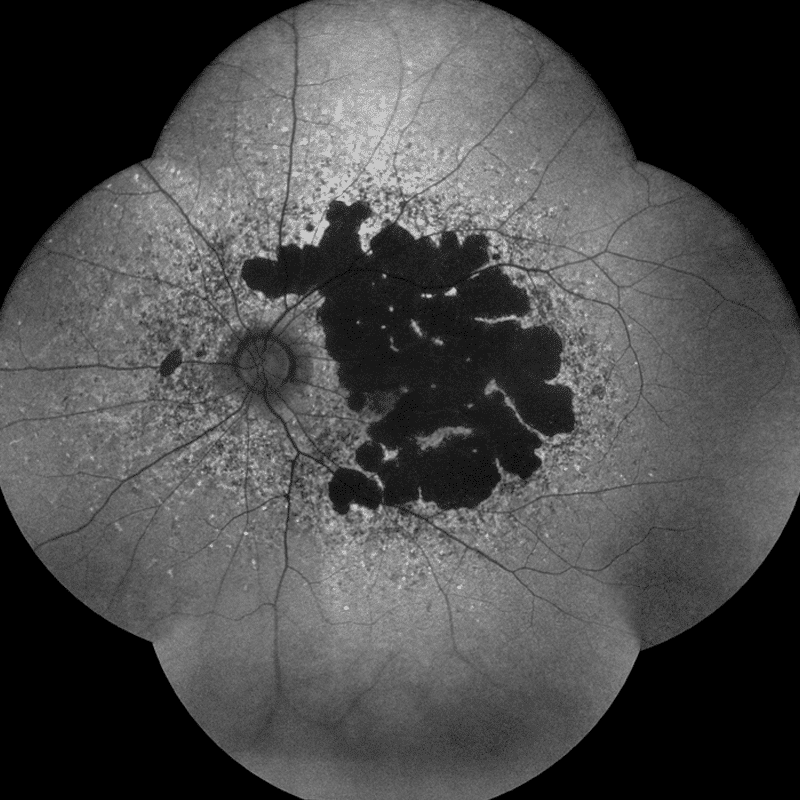

A Ultra-Widefield Module Lens is also available as an accessory, using TrueColor confocal technology to give unsurpassed image quality and a superior increased field of view of the retina. A single image with the lens can get 120° and takes less than a minute, and a mosaique style image can be quickly taken to show 200° in a panoramic view. (Optional extra)

Widefield acquisition

Not only does the EIDON AF have a fantastic range of imaging modalities at its disposal, it also offers high-quality, crisp widefield imaging. It can achieve up to 110° thanks to the unique mosaic functionality. This widefield image function is available for all of its imaging modalities. Widefield imaging is crucial in diagnosing pathologies that may initially present in the periphery.